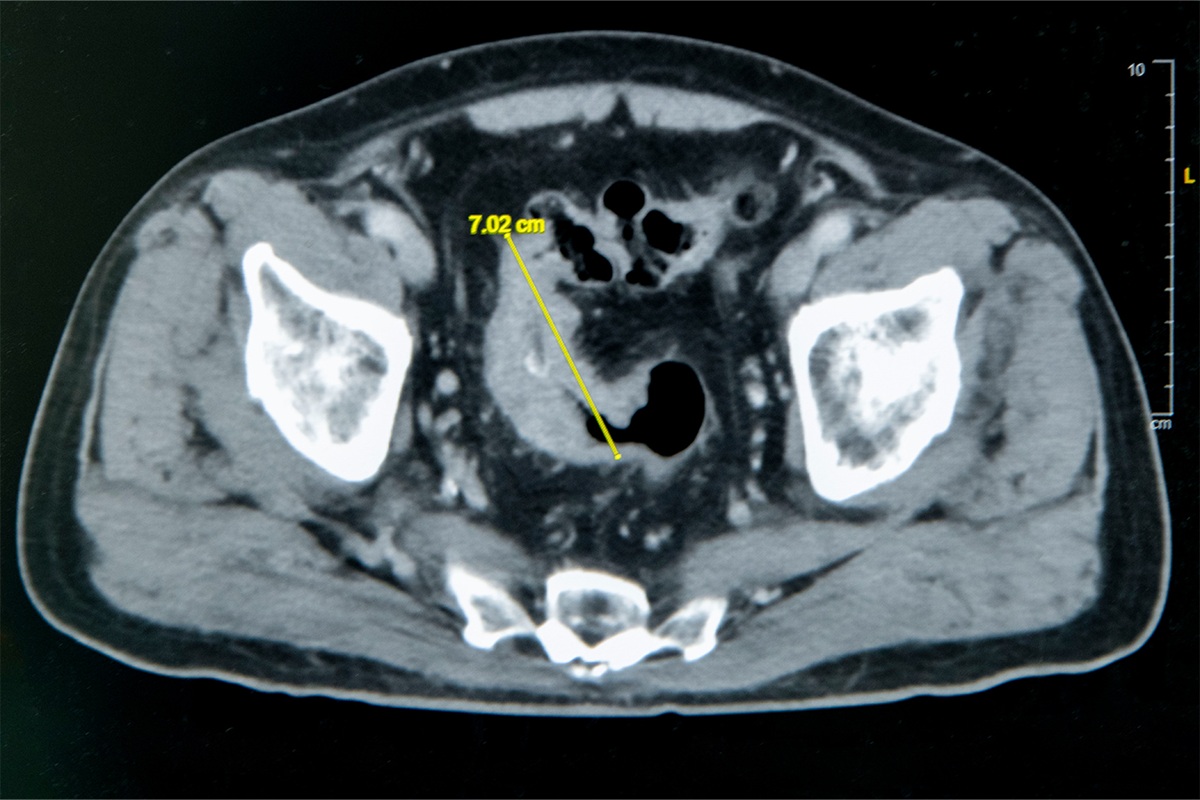

大腸直腸外科主任張譽耀醫師表示,老翁罹患乙狀結腸癌,腫瘤約7公分造成腸子幾乎完全阻塞,也導致老翁一進食就會肚子又脹又痛;術前因為不敢進食,老翁體重下降、營養不足,也可能造成傷口癒合不良。老翁的手術其實會有兩個傷口,一個是肚子上的傷口、一個腸子的傷口,若腸子傷口癒合不良會造成腸吻合滲漏,到時就必須做人工肛門了!所幸經過提早住院,透過靜脈營養針先建立營養,讓病人強健身體後才手術,術後傷口果然順利癒合。